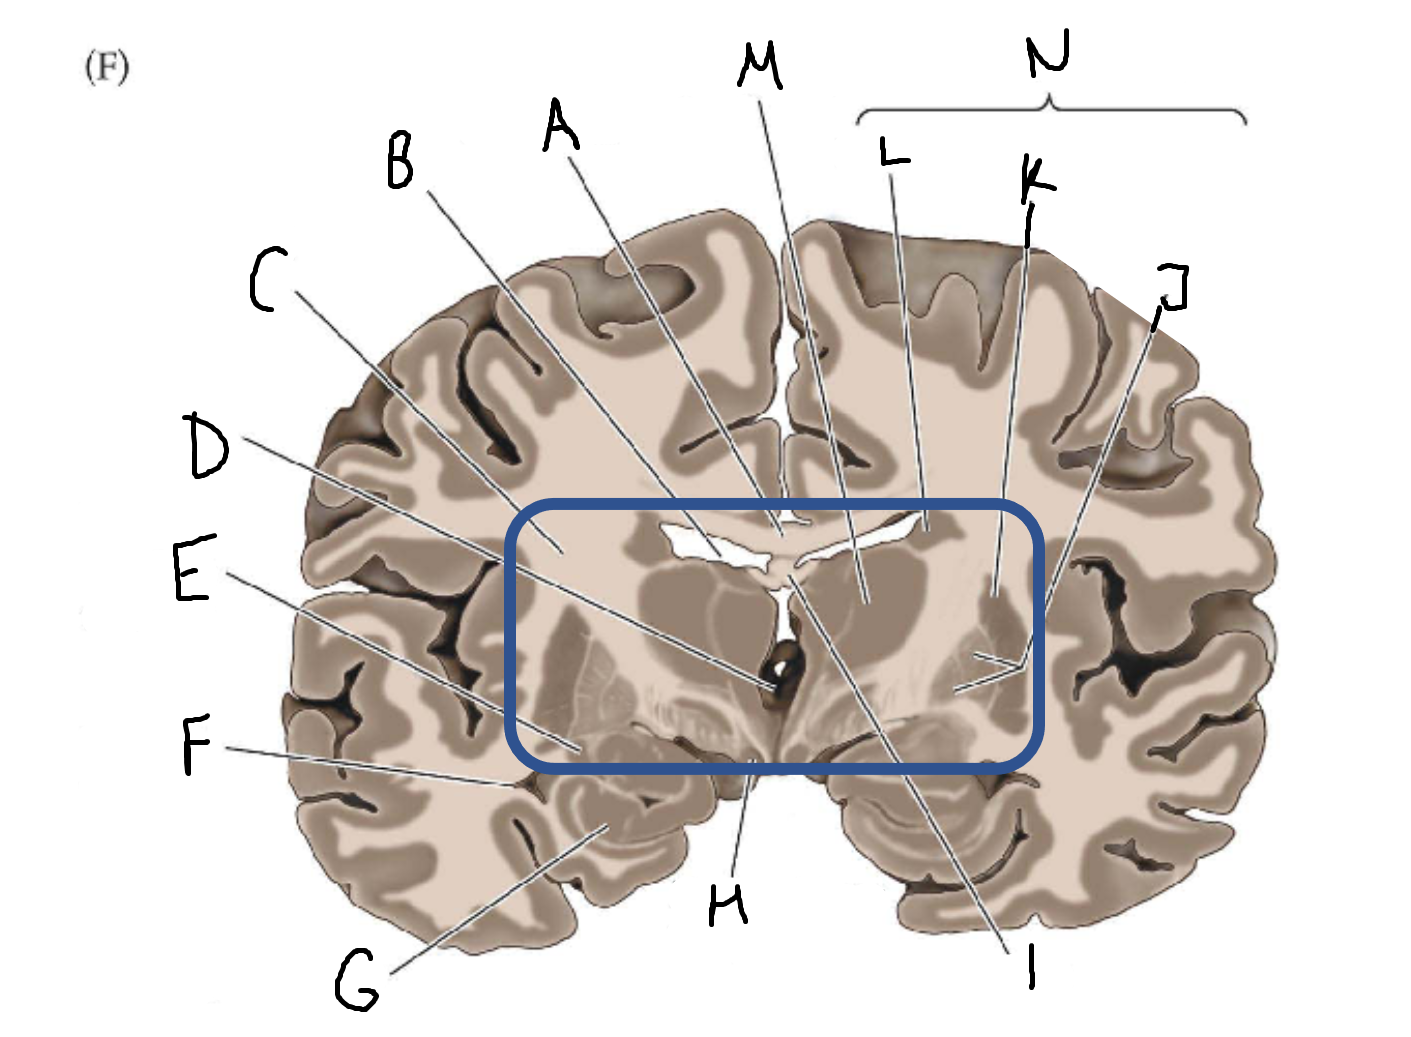

A

corpus callosum

B

lateral ventricle

C

internal capsule

D

third ventricle

E

tail of caudate nucleus

F

lateral ventricle

G

hippocampus

H

mammillary body

I

fornix

J

globus pallidus

K

putamen

L

caudate

M

thalamus

N

basal ganglia